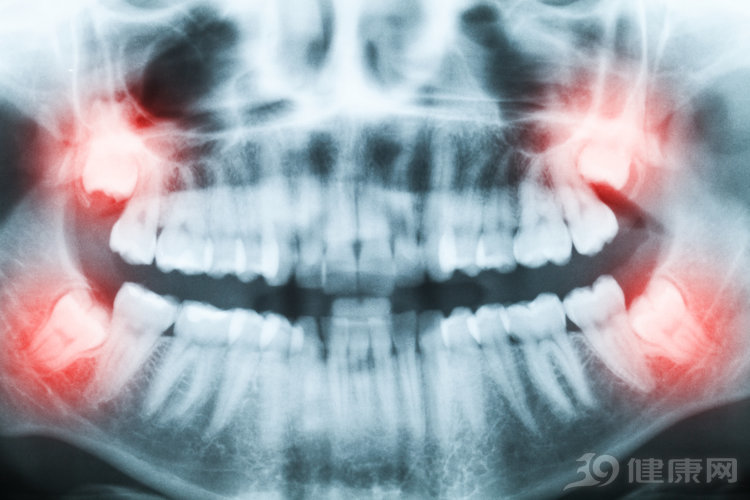

l 智齿冠周炎

一般人在18岁以后就会开始萌发智齿或第三磨牙。而智齿在萌出的过程中会被牙龈瓣覆盖成一个盲袋,食物残渣就易集聚,从而难以清洁,最终导致牙齿反复发炎而形成冠周炎。